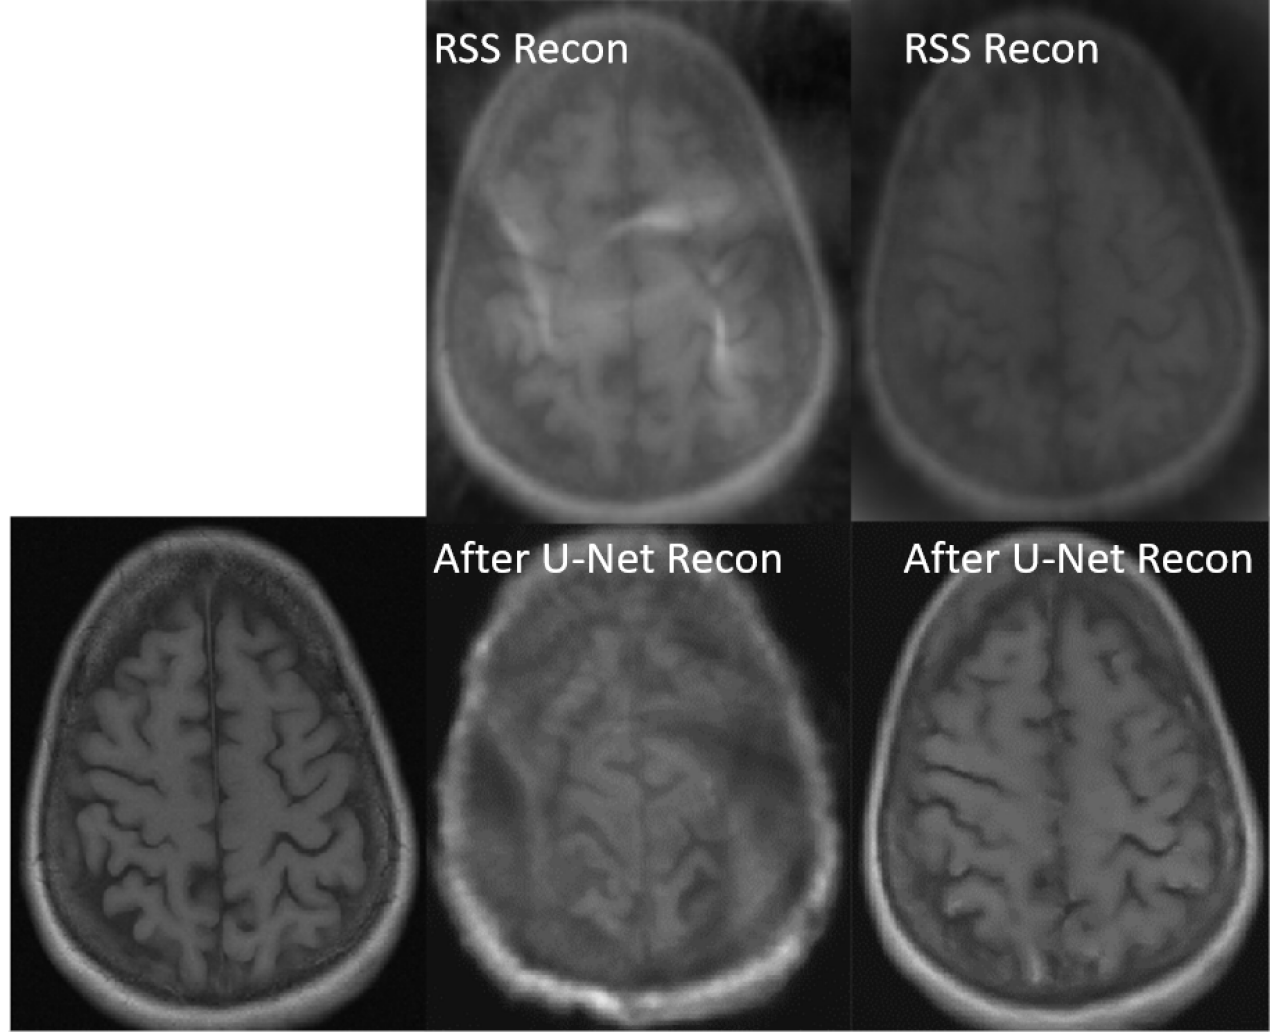

The reconstructed images from the learned trajectories using radial trajectory were demonstrated in Figure 4. These images were compared with the images directly reconstructed using fixed trajectory. The framework was slightly modified by removing the trajectory optimization network and only training the end-to-end reconstruction U-Net using the standard supervised learning approach. The qualitative evaluation of brain images proves the improved image reconstruction using our proposed method. As illustrated in Figure 4, the reconstructed images from learned trajectories are consistently better than those from the fixed trajectories for each type. More specifically, the learned radial trajectories provided improved reconstruction performance compared to their fixed counterparts in Figure 4 for the brain images at the AXT1POST sequence (More results in Appendix). Notably, the intermediate images directly obtained from the RSS reconstruction were shown at the top row of Figure 4 for the learned and fixed trajectories. It is evident that the learned trajectory can better remove structural and aliasing artifacts and provided more realistic image features and accurate image contrast than that of the fixed trajectory at the same level of acceleration, indicating the efficacy of the learning-based trajectory optimization.

The reconstructed images from the learned trajectories using Cartesian, and spiral trajectories were demonstrated in Figures 8, and 9, respectively. These images were compared with the images directly reconstructed using fixed trajectory. The framework was slightly modified by removing the trajectory optimization network and only training the end-to-end reconstruction U-Net using the standard supervised learning approach. The qualitative evaluation of knee and brain images proves the improved image reconstruction using our proposed method. As illustrated in Figures 8, and 9, the reconstructed images from learned trajectories are consistently better than those from the fixed trajectories for each type. More specifically, Figure 8 provides an example of a reconstructed knee image using a learned Cartesian trajectory at an acceleration factor (AF) of 4.4. This figure shows that the learned trajectory provides better image features, improved image sharpness, and more detail recovery due to their optimized k-space coverage. The learned Cartesian trajectory outperformed the regular Cartesian trajectory at the same acceleration rate. Likewise, the learned spiral trajectories provided improved reconstruction performance compared to their fixed counterparts in Figure 9 for the brain images at the AXT1 sequence. Notably, the intermediate images directly obtained from the RSS reconstruction were shown at the top row of Figures 8, and 9 for the learned and fixed trajectories. It is evident that the learned trajectory can better remove structural and aliasing artifacts and provided more realistic image features and accurate image contrast than that of the fixed trajectory at the same level of acceleration, indicating the efficacy of the learning-based trajectory optimization.